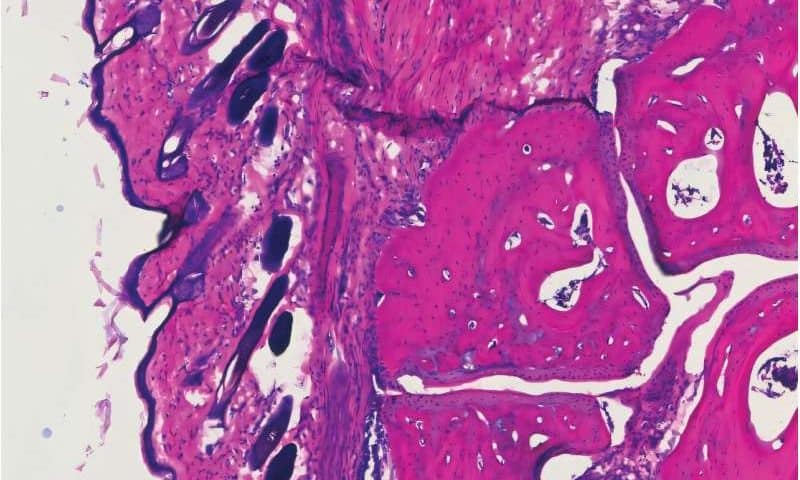

They next engineered a recombinantly expressed IgG to have enhanced binding to these receptors and infused them into mice with human Fc receptors into which they had induced arthritis (meaning they’d been injected with serum isolated from a mouse with naturally occurring arthritis). A similar group of arthritic mice was treated with the conventional IVIG infusion.

A second test run used a mouse model stand-in for multiple sclerosis, an autoimmune disease that causes both cognitive and mobility deterioration. The molecule protected mice from neuro-inflammation by preventing cell destruction, and did so at the same small dose.